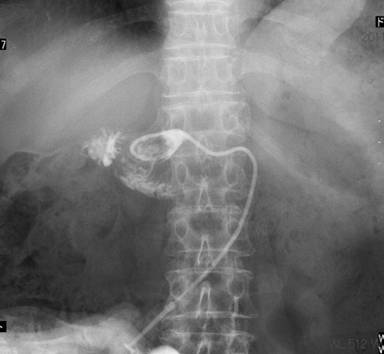

A 62-year-old woman with abdominal pain was found to have a lower biliary carcinoma. A pylorus-preserving pancreaticoduodenectomy (using the Traverso technique) with a lymph node dissection was performed. Pancreaticojejunal anastomosis was performed in an end-to-side fashion. The pancreatic duct and the jejunal mucosa were fixed. The stump of the pancreas and the jejunal wall were approximated with interrupted sutures, which were inserted through the anterior wall of the pancreas through the pancreatic parenchyma to the posterior wall. Sutures were then passed through the seromuscular layer of the jejunum, in the posterior-to-anterior direction, wide enough to cover the cut surface of the pancreas. A catheter with multiple side-holes was inserted into the pancreatic duct and sutured into place as an external stent. The stent tube was guided externally through the stump of the jejunal loop and fixed to the abdominal wall. Histological and immunohistochemical studies resulted in the diagnosis of a biliary carcinoma with lymph node metastases. The postoperative course was uneventful and the patient was discharged from the hospital 16 days postoperatively. The external stent of the pancreatic duct was removed on the 28th postoperative day. After removal, there was no output of fluid from the drain. After discharge, the patient was followed up with computed tomography (CT), ultrasonography (US), and laboratory examinations every 3 months in the outpatient ward. No notable findings were obtained (Figure 1). One year after surgery, she was admitted to our hospital for abdominal pain. All laboratory parameters, including the serum levels of tumor markers, were normal. Abdominal CT and US revealed a fluid collection around the pancreaticojejunal anastomosis (Figure 2). The size of the fluid collection was 45x33x20 mm. US-guided drainage of the fluid collection was performed. A catheter was inserted percutaneously and the fluid collection was drained. Discharge showed a gram-negative rod in the culture, and the amylase value of the discharge was significantly elevated (119,500 IU/L). Contrast radiography of the drainage tube showed no significant collection (Figure 3) and the tube was clamped. The patient was discharged from the hospital without symptoms. We evaluated the pancreatic fistula by CT and US. There was no fluid collection around the pancreaticojejunostomy.

Figure 3. Fistulography showing the disappearance of the fluid collection around the pancreaticojejunal anastomosis. We confirmed the presence of an internal fistula into the intestine. |

In our case, postoperative examinations in the follow-up period showed no recurrence and no metastasis after the pancreaticoduodenectomy. One year later, the patient suffered from abdominal pain and fluid collection in front of the pancreaticojejunal anastomosis, as detected by CT and US. Fortunately, the fluid collection flowed from the surface of the anastomosis. Percutaneous US-guided drainage was performed easily. One week later, a fistulography showed the disappearance of the fluid collection around the pancreaticojejunal anastomosis, and we confirmed the internal fistula into the intestine. Most pancreatic fistulas are managed non-operatively by conservative treatment. However, surgical treatment is sometimes required [20]. The exact reason for a delayed pancreatic fistula is unclear. But, it appears that a small initial amount of leakage is aggravated by infection. Barreto et al. [21] discussed the gray zone between a pancreatic fistula and post-operative collections. They suggested that the causes of a delayed pancreatic fistula were drains failing to drain due to blockage, displaced or misplaced drains, and vascular factors.